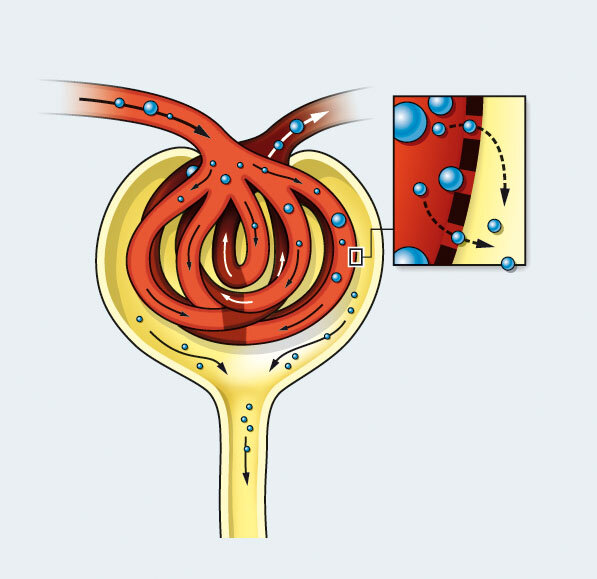

Bei der Glomerulonephritis handelt es sich um eine Entzündung der Nierenkörperchen (Glomeruli). Die Nierenkörperchen bestehen aus einer Art Gefäßknäuel in der Nierenrinde (siehe auch Hintergrundinformation weiter unten), in denen der sogenannte Primärharn gebildet wird. Unterteilt werden die Glomerulonephritiden in eine primäre oder sekundäre Glomerulonephritis. Handelt es sich um eine Entzündung der Nierenkörperchen, ohne weitere Systemerkrankung spricht man von einer primären Glomerulonephritis, ist die Entzündung dagegen Folge einer anderen Erkrankung außerhalb der Nieren, handelt es sich um eine sekundäre Glomerulonephritis.

Bei einer Nierenentzündung können aber auch die Harnkanälchen (Tubuli) und der sie umgebende Raum (Tubulointerstitium) entzündet sein, dann ist von einer tubulo-interstitiellen Nephritis die Rede. Als Folge davon treten Störungen in der Konzentrierung des Primärharnes auf.